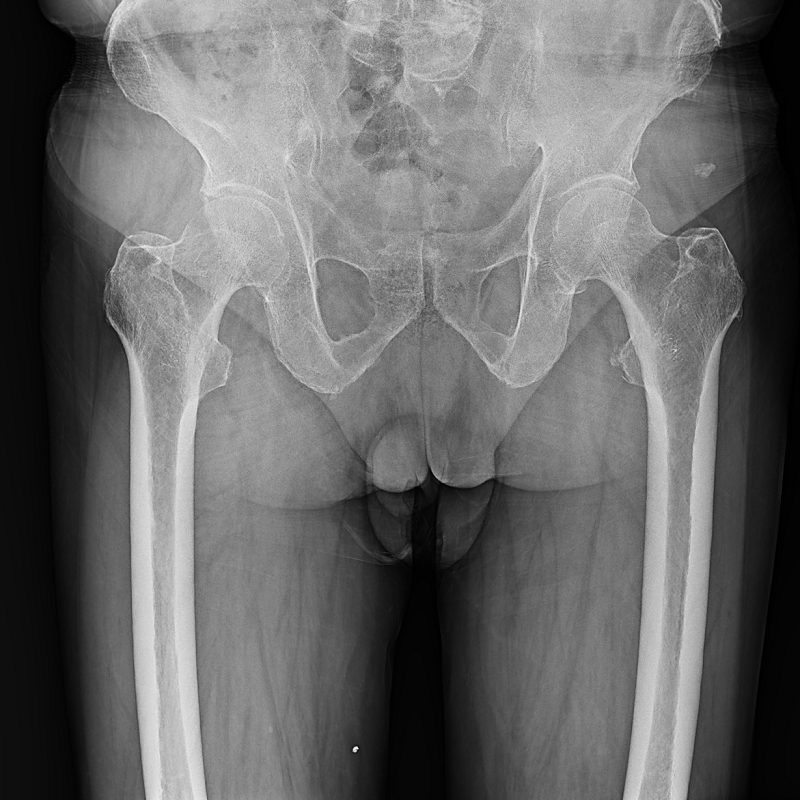

●呈現全下肢或全脊柱圖像

●在脊柱及下肢畸形矯正手術(shù)治療中,為術(shù)前方案制定和術(shù)后復查提供精準測量

●有效解決傳統X光片不能一次成像問(wèn)題,為患者提供更加優(yōu)質(zhì)的醫療服務(wù)